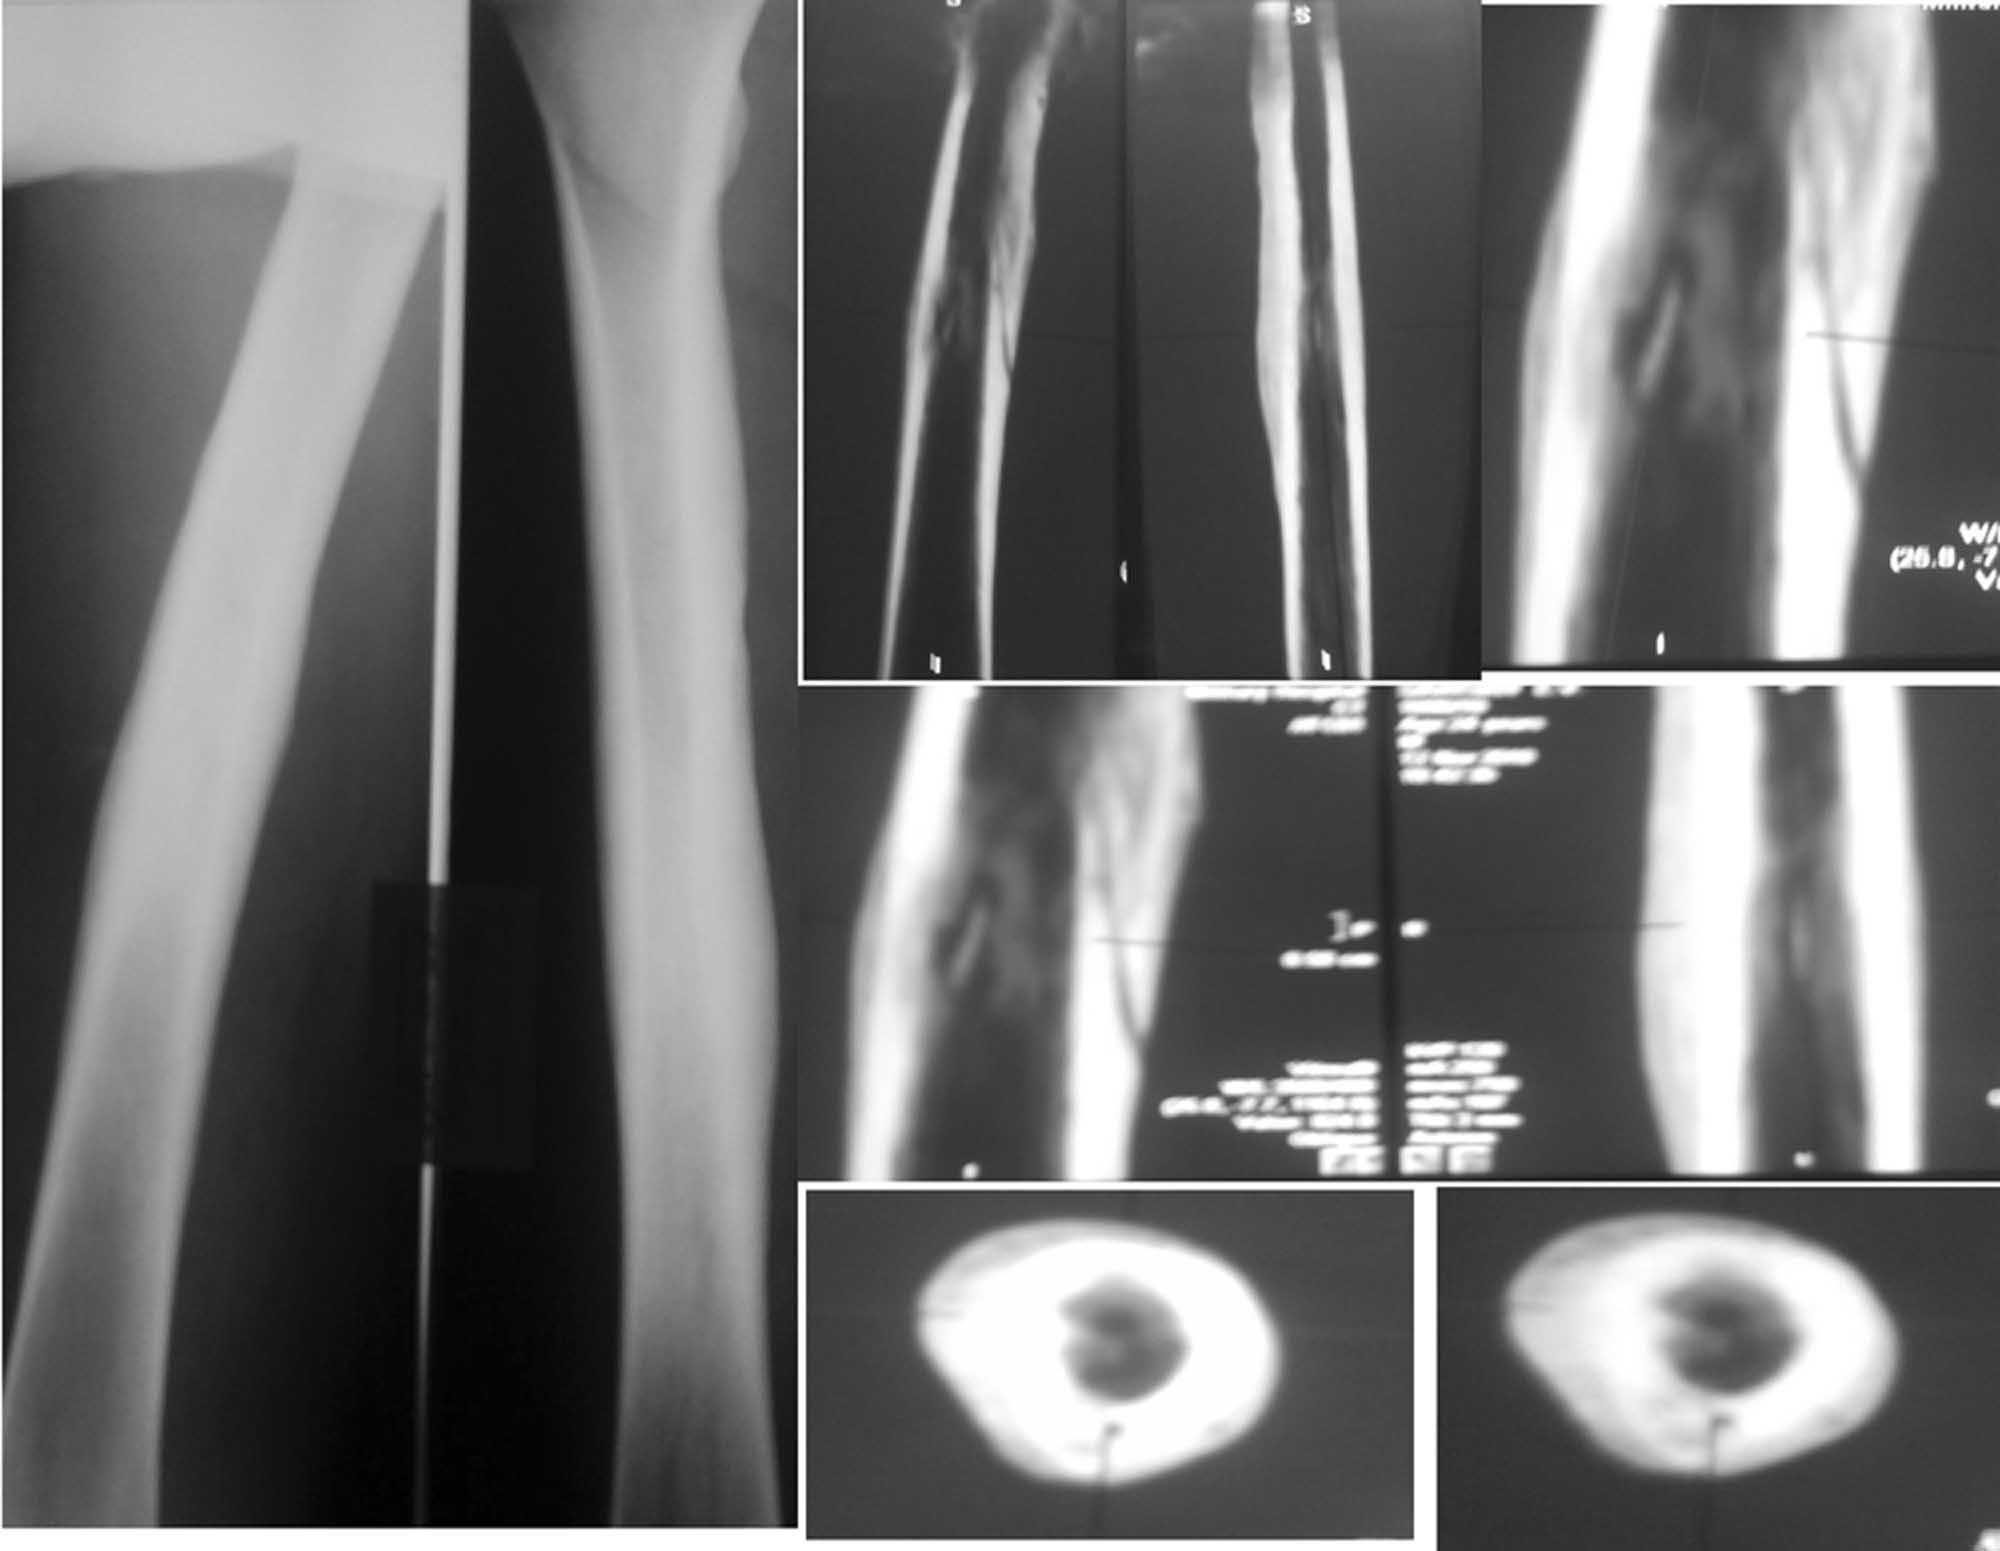

Последующие 2 года ничего не беспокоило. Около 2 недель назад появились боли и припухлость в нижней трети правого бедра, вновь без видимой причины. На рентгенограммах бедра выявлены выраженная периостальная реакция, на КТ признаки хронического гематогенного остеомиелита.

Моё мнение, что это хронический(гематогенный) остеомиелит правого бедра в ср. трети, секвестральная, безсвищевая форма. возможно происходит формирование ещё и секвестра наружного кортикала.